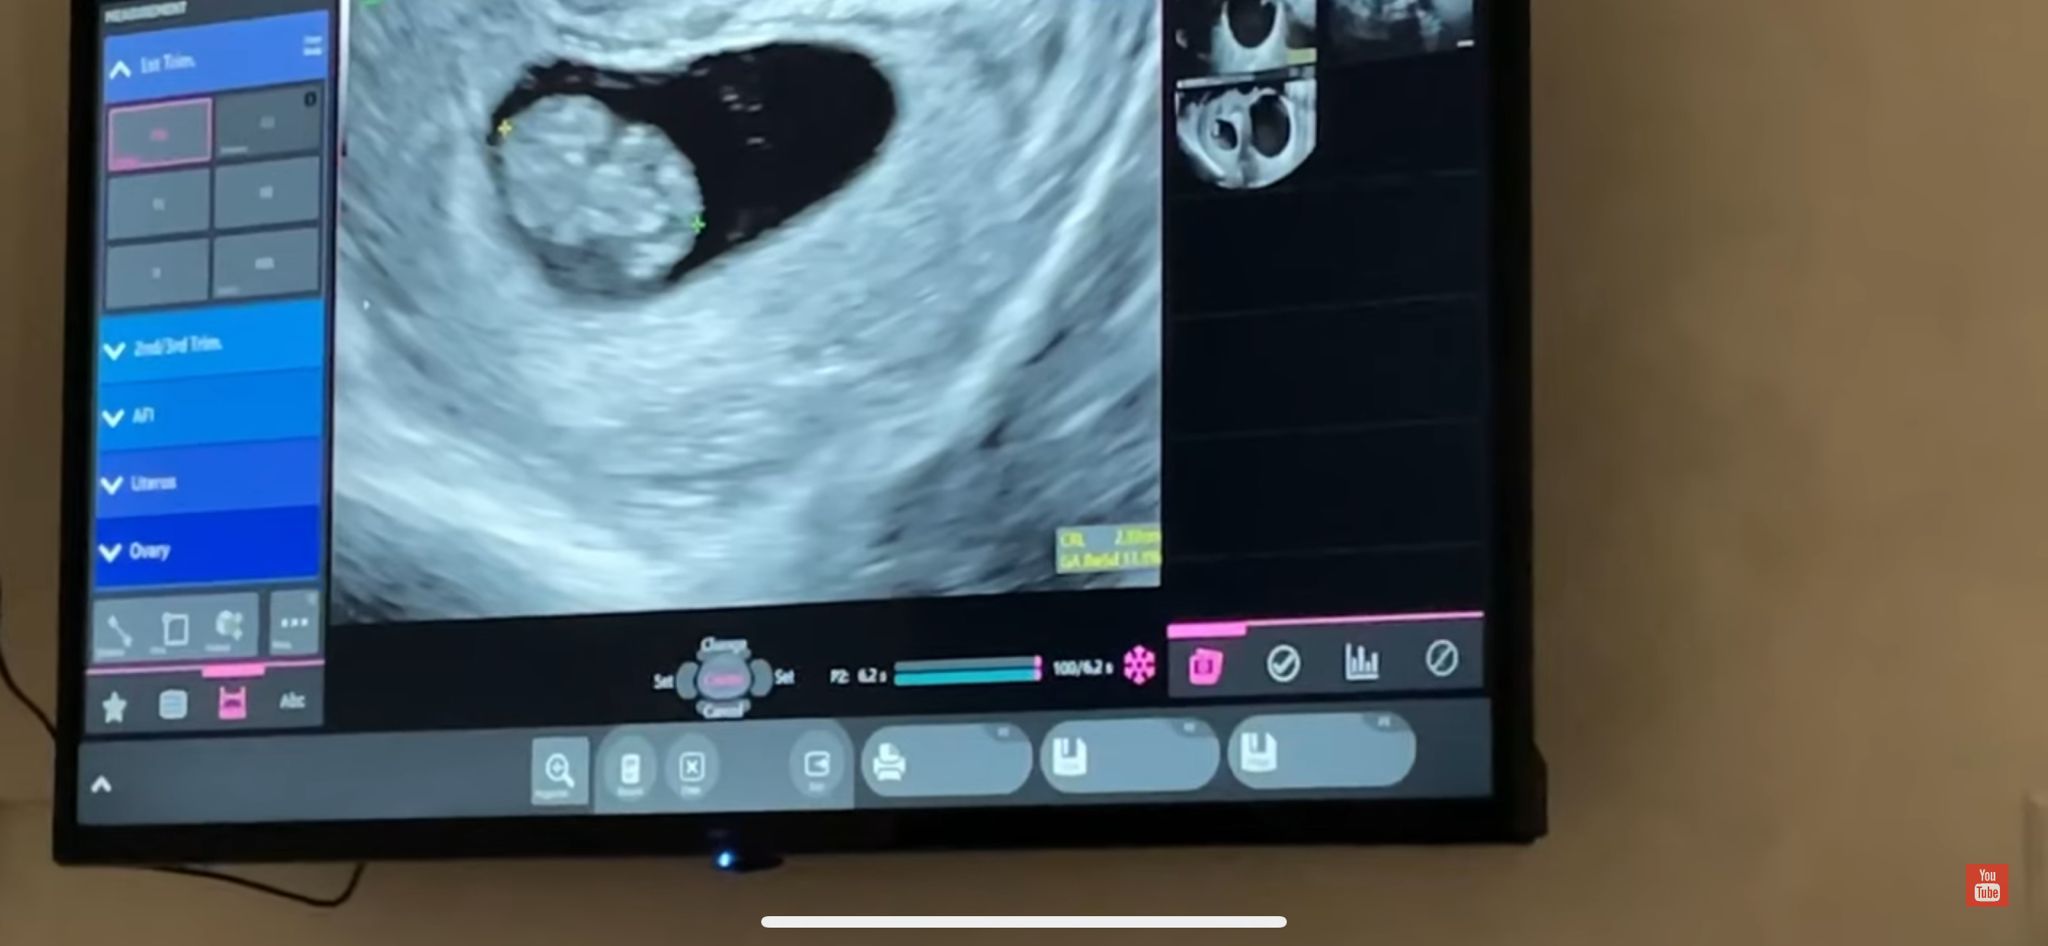

Nu de puține ori, Mary s-a jucat puțin cu dorința puternică a iubitului ei de a deveni tată. Astfel că Robert s-a lovit de mai multe farse în care fosta concurentă de la „Puterea dragostei” îl păcălea că este însărcinată. Așa că atunci când Marinela Mavrodin l-a anunțat că este cu adevărat gravidă, tânărul aproape că nu a crezut-o. Iată momentul emoționant, când a aflat că va deveni tată!

Marinela Mavrodin a pregătit în cel mai mic detaliu momentul în care i-a dezvăluit partenerului ei de viață că este însărcinată. I-a scris o scrisoare absolut emoționantă și i-a pus testul de sarcină, care indica două liniuțe, într-o cutie de cadou.